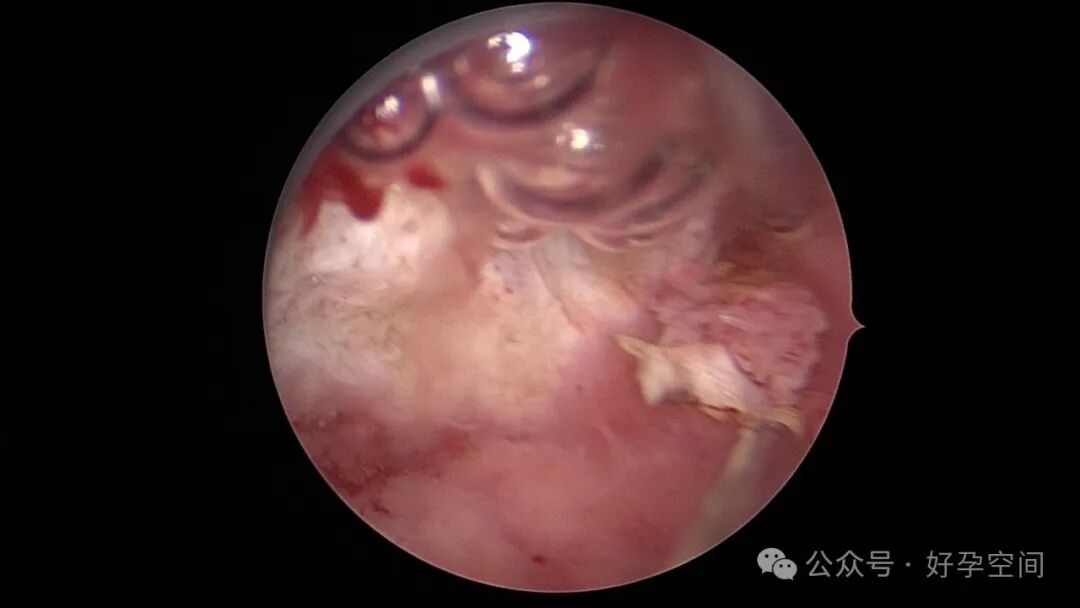

患者24岁,G6P3,顺产1次,双胎剖宫产1次。本次停经53天,计划外妊娠,行宫腔镜取胚及安环术。摘除胚胎后见宫腔右侧壁胚胎附着部位包块,约1.0cm*1.0cm*0.8cm,宫腔镜切除包块送病检,放置γ环一个,环两臂卷曲于右侧宫角,宫腔镜钩住环尾部下拉,上推节育环右臂,将环调整到正常位置。术后病检结果为“宫腔胎盘附着部位超常反应”。

超常胎盘部位(exaggerated placental site,EPS)反应是指在胎盘附着部位组织的过度反应性病变。1991年,WHO将其列入滋养细胞疾病,但目前国内外对该病的诊断尚无统一标准。在正常妊娠中,中间型滋养细胞可侵入底蜕膜或浅肌层,而超常胎盘部位反应时,中间型滋养细胞在胎盘部位大量浸润,并侵入子宫肌层,是正常胎盘反应的加剧,是一种滋养细胞疾病。EPS反应可发生于正常妊娠、流产或葡萄胎后,发生于葡萄胎者浸润力更为明显。EPS以病理诊断为依据,其组织学特征以中间型滋养细胞为主,由子宫内膜向肌层的良性漫润,不破坏原有组织结构,伴有淋巴细胞灶性浸润。EPS是一种非肿瘤性的良性滋养细胞疾病,普通人工流产、宫腔镜取胚或产后出血增多,手术医生主观感觉宫腔已经清理干净,但B超提示宫内占位包块,应考虑到是否存在EPS,建议做宫腔镜探查,切除包块送病检,以明确诊断,避免遗漏其他严重疾病,EPS对症治疗即可,观察病情变化,预后良好。